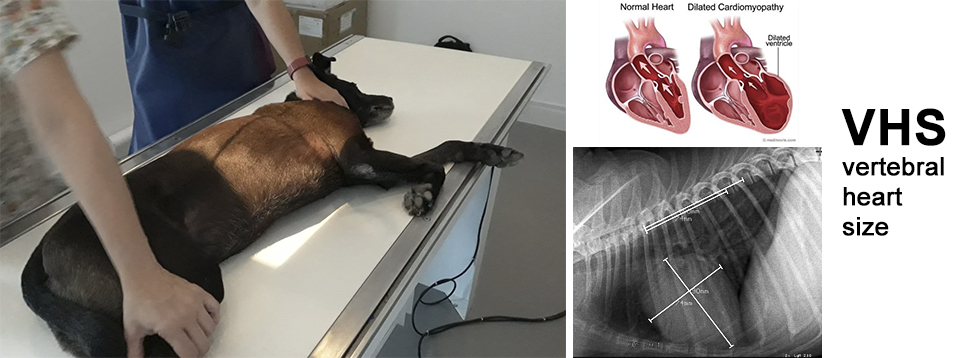

Radiologia Digital Direta / Digital Radiography

As radiografias geradas digitalmente podem ser transmitidas para iPad Apple®, notebooks e smartphones.

iPad com tela Retina Apple® possibilita a visualização das imagens com maior qualidade diagnóstica.

O treinamento aborda a geração das radiografias, a edição digital das imagens, e também a

escolha adequada de técnicas radiográficas como kilovoltagem, corrente elétrica e tempo de exposição.